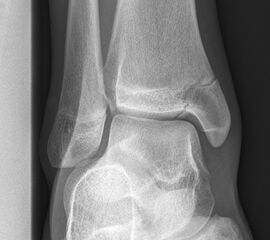

Sprunggelenk anterior-posterior (ap) ohne Belastung

Positionierung:

• Das Sprunggelenk befindet sich in 90° Stellung, das Bein ist gestreckt.

• Die Zehen sind direkt nach oben gerichtet.

• Der Zentralstrahl ist mittig auf den Gelenkspalt am oberen Sprunggelenk zentriert.

• Der Röntgenfilm liegt horizontal.

Kennzeichen des Röntgenbildes:

• Der Talus ist leicht außenrotiert.

• Der talofibulare Gelenkspalt wird partiell durch die distale Fibula überdeckt.

• Das anteriore Tuberkel der Tibia überlappt die distale Fibula.

Besondere Bemerkungen zum Beispielbild:

• Innenknöchelfraktur bei einem Jugendlichen.

• Keine relevante Dislokation.

• Die Wachstumsfugen sind noch erkennbar, im Wesentlichen aber geschlossen.